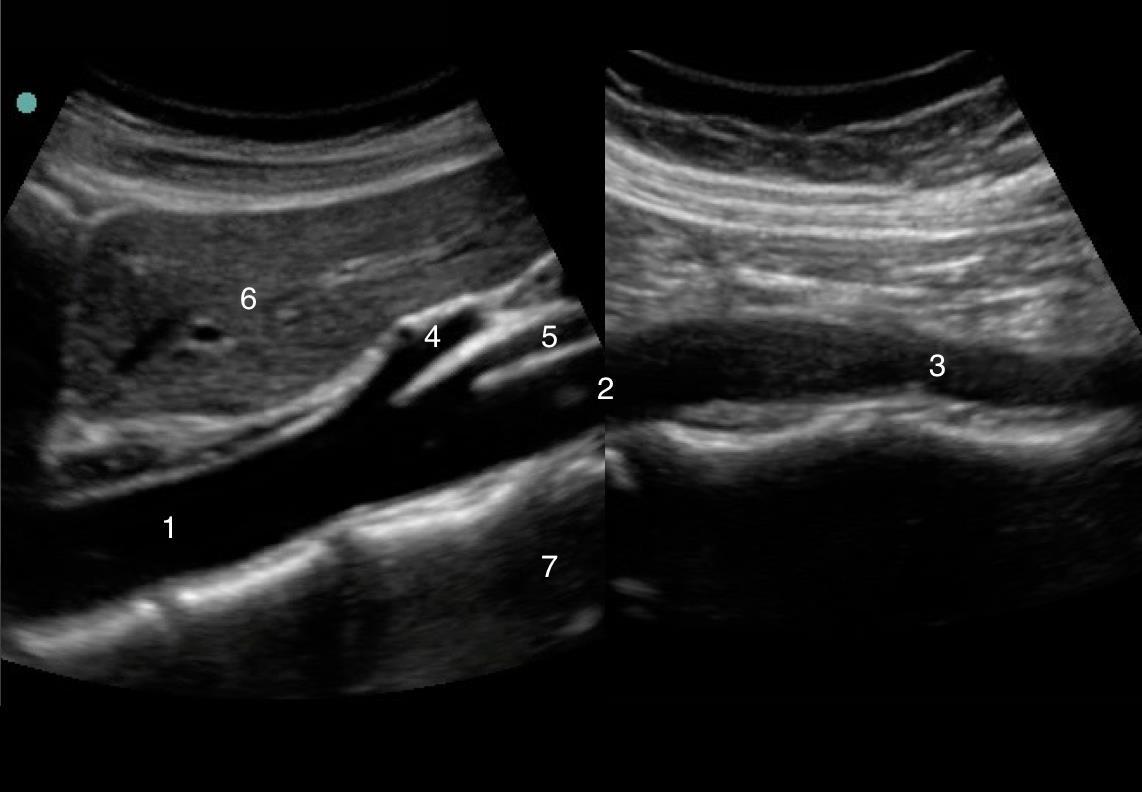

Imagen 2 longitudinal de la aorta

1. Aorta (Ao)

2. Aorta media (Ao)

3. Aorta distal (Ao)

4. Tronco celíaco

5. Arteria mesentérica superior (AMS)

6. Hígado

7. Columna